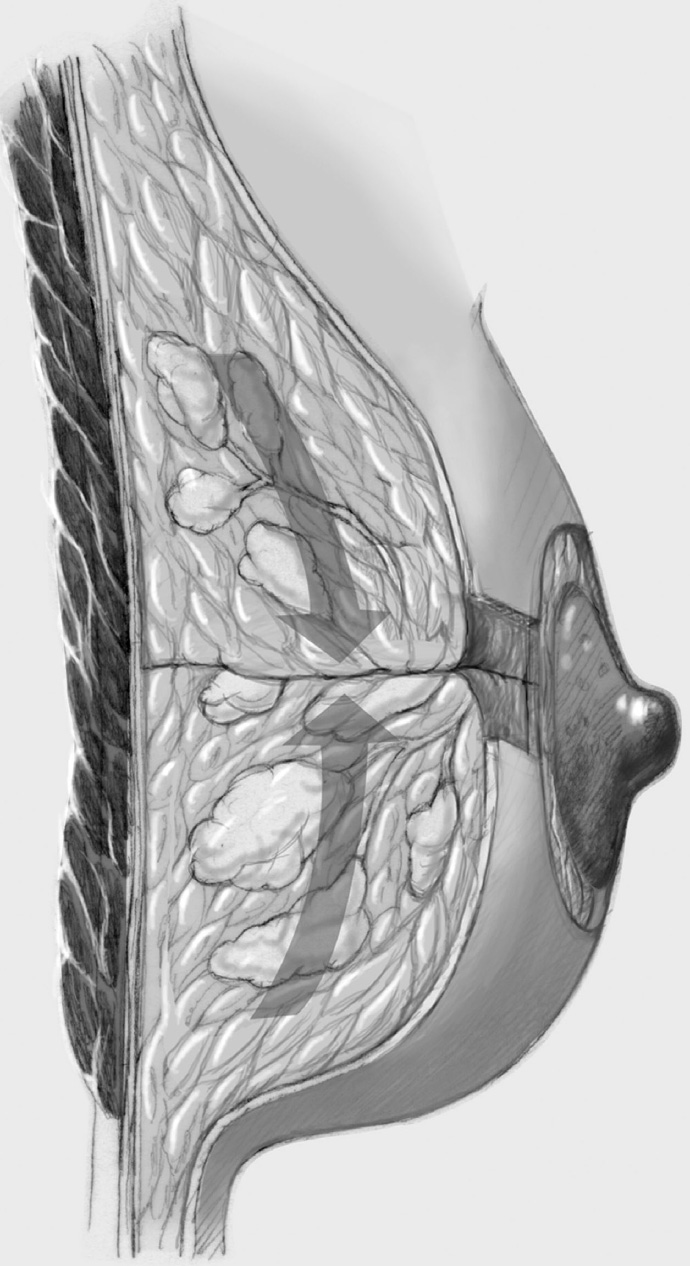

Operation classification. Although the principles of all breast-conserving surgical techniques are similar, it is important for scientific and didactic reasons and not least for documentation to use uniform nomenclature for these operations. The classification given in Chapter 1.2.2 distinguishes between “simple,”“complex,” and “oncoplastic” operations. Simple BCS is histologically confirmed tumor excision (wide local excision to quadrantectomy) where the defect is covered by direct approximation alone, without mobilization of glandular tissue or skin flaps. Complex BCS is defined as histologically confirmed tumor excision (wide local excision to quadrantectomy) with intramammary reconstruction of the breast by subcutaneous or epifascial mobilization of glandular tissue to fill the defect, and with mobilization of a skin flap if necessary (< 25% mobilization). Oncoplastic BCS corresponds to complex BCS but with a mobilization volume greater than 25%. Periareolar de-epithelialization patterns to move the nipple are outside the limits of the various complex oncoplastic breast-conserving procedures (Chapter 3.2.2).

The same principles apply as in simple breast-conserving treatment though the size of the tumor necessitates more extensive segmental resection or even quadrant resection, which requires internal breast reconstruction with more complex defect cover by lobes of the breast. Often, more skin has to be resected to match the reduction in the size of the breast produced by the operation. Only the last step of periareolar de-epithelialization and nipple repositioning—that is, complex oncoplastic breast-conserving treatment—is not performed.

The adjacent parenchyma is mobilized subcutaneously so that the defect can be filled with lobes of breast tissue. Mobilization means exposing the breast relative to the skin or muscle to achieve adequate mobility of < 25% or > 25% as required.

To cover the defect, the glandular lobes are mobilized from the adjacent parenchyma after subcutaneous dissection. The principle of intramammary lobe creation is to mobilize large parts of the breast (> 25%) either relative to the skin or relative to the pectoralis muscle. This “liberation” of the breast from one of its two planes of fixation allows adequate dissection and rotation of sufficient breast tissue. The Y-flap and rotation flap shown in Chapter 3.2.1 are examples of intramammary dissection.

When the breast is mobilized subcutaneously, it must be ensured that both the dissected skin layer and the breast tissue are sufficiently thick. For the layer of breast tissue, a minimum thickness of 1 cm is desirable. The ratio of base to length must also be considered.